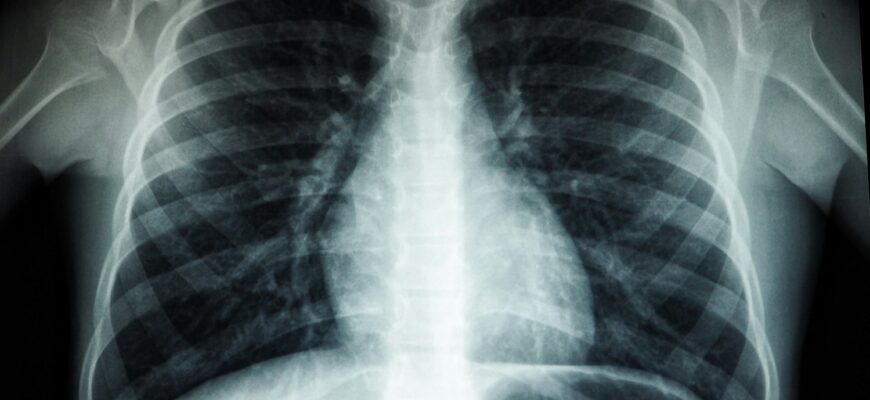

În cadrul activităților, fiecare persoană a completat chestionarul de screening și a semnat acordul informat. Persoanele care au efectuat investigația radiologică au fost informate despre riscurile tuberculozei, măsurile de prevenire, importanța depistării precoce, precum și despre posibilitățile de a efectua gratuit tratamentul.

În total, au fost examinate peste trei mii de persoane, dintre care 146 au fost identificate ca suspecte de tuberculoză. În urma investigațiilor suplimentare, au fost confirmate 27 de cazuri de TB, care au fost incluse în tratament. Rezultatele investigațiilor radiologice au fost comunicate sistematic instituțiilor de asistență medicală primară, iar persoanele suspecte sau cu alte patologii au fost luate la evidență și monitorizate de medicul de familie și medicul ftiziopneumolog.